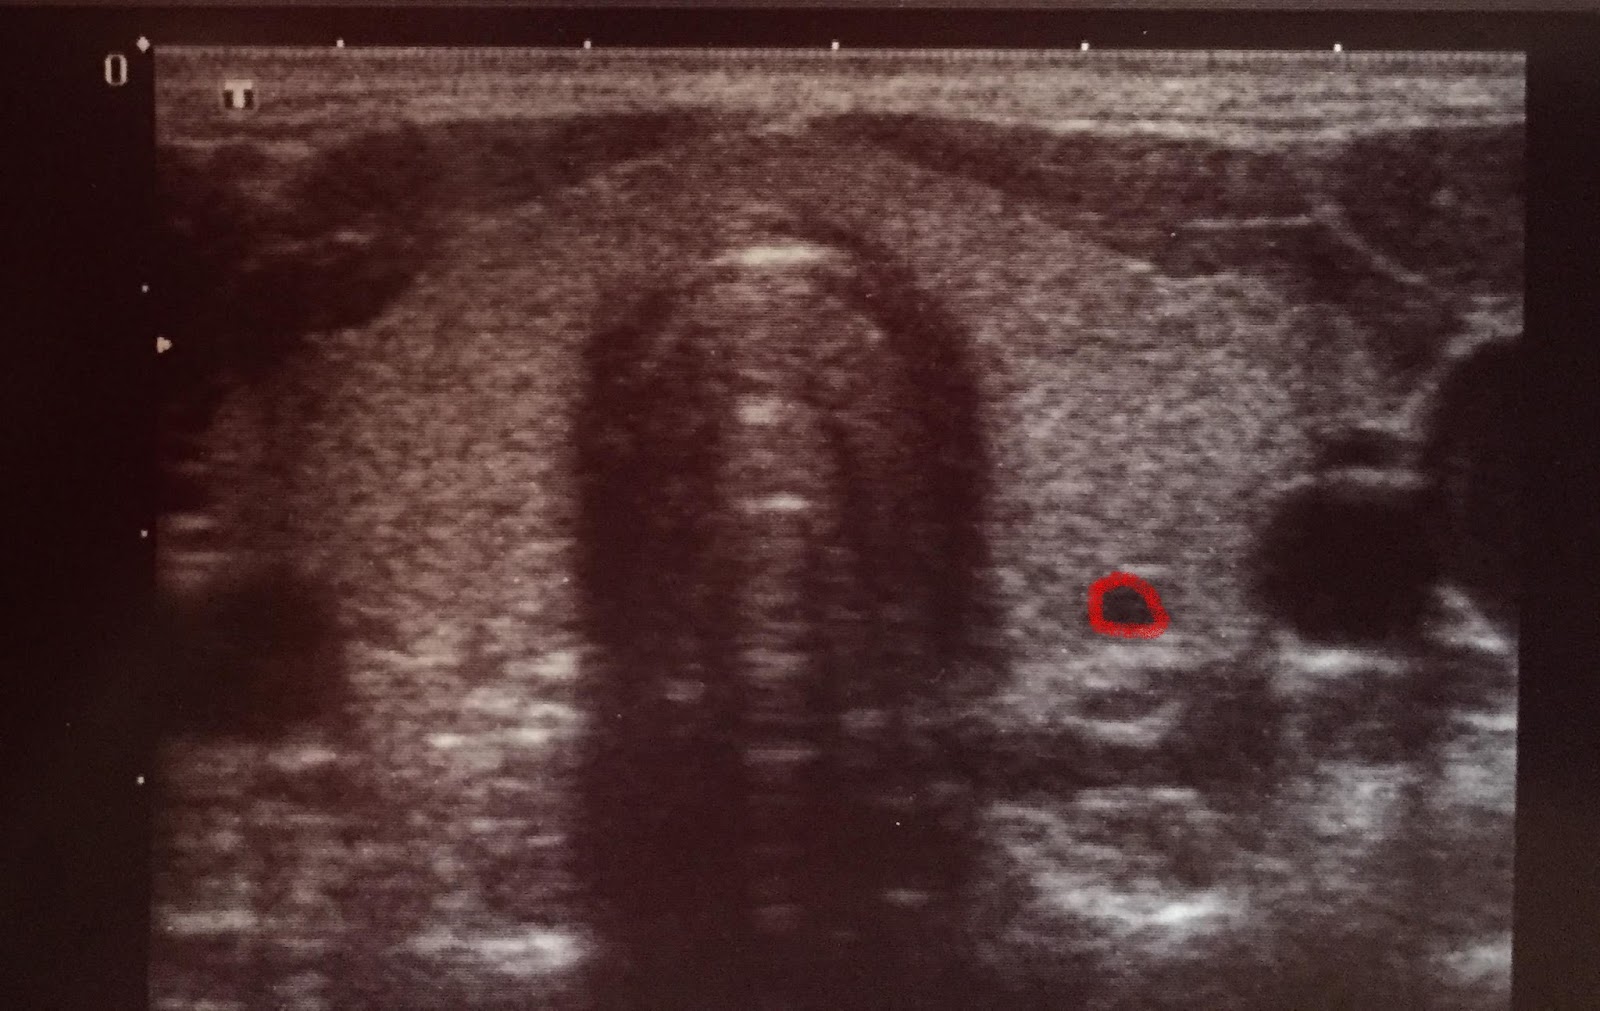

![]() |

| wydaje Ci się, że to też guzek? |

| ten sam, zaznaczony na czerwono. w rzeczywistości to naczynie krwionośne „w przekroju” |